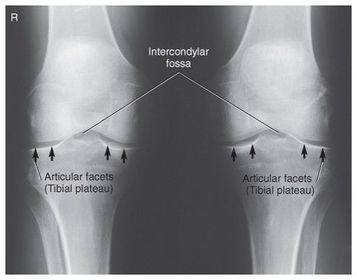

A. medial and lateral intercondylar tubercles B. lateral epicondyle femur C. lateral condyle femur D. lateral condyle tibia E. articular facets tibia (tibial plateau) F. medial condyle tibia G. medial condyle femur H. medial epicondyle femur I. patella

The articular facets making up the tibial plateau slopes posteriorly at _____ 10-20 degrees